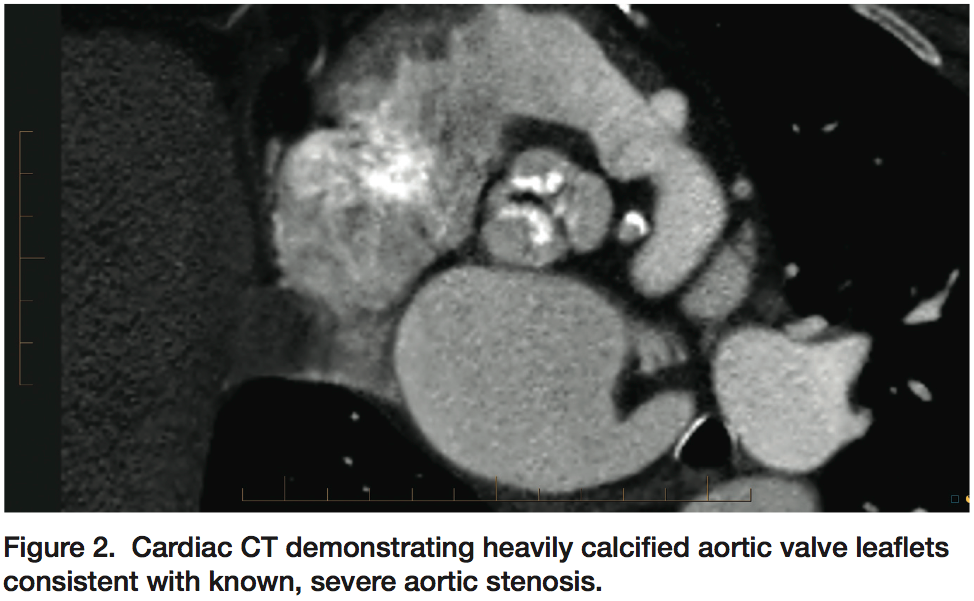

Given these considerations, she was felt to be an appropriate candidate for transfemoral TAVR and comprehensive pre-procedural testing was performed at Oklahoma Heart Institute, including transthoracic and transesophageal echocardiography, cardiac catheterization with coronary and bypass graft angiography, as well as computed tomographic (CT) evaluation of the aortic valve/annulus, aorta and iliofemoral vessels (Figures 2-5). These studies were performed, interpreted and reviewed by the multidisciplinary Heart Team at Oklahoma Heart Institute, and the patient was felt to be an appropriate candidate for transfemoral TAVR utilizing a 23 mm Edwards Sapien transcatheter heart valve.

Yes. This procedure is complex enough that it necessitates all that testing be done before we can even know if a patient is a candidate. Patients must have coronary angiography and a cardiac cath to evaluate their coronary anatomy, aorta and iliac vessels. Similarly, a CT scan is done to assess their native aortic valve and annulus size, and assess for suitability of transfemoral access. We try to space all those procedures out over the course of weeks to mitigate the risk of contrast-induced nephropathy. Clearly each of these procedures, cath, CT, and TAVR, have radiation associated with them. However the radiation doses are small with each of these tests, and these patients are relatively elderly, so things like the risk of cancer due to procedural radiation are not a big concern. The deterministic effects of radiation are always a concern, but we strive very hard to limit radiation doses and thus far we have not had a problem.